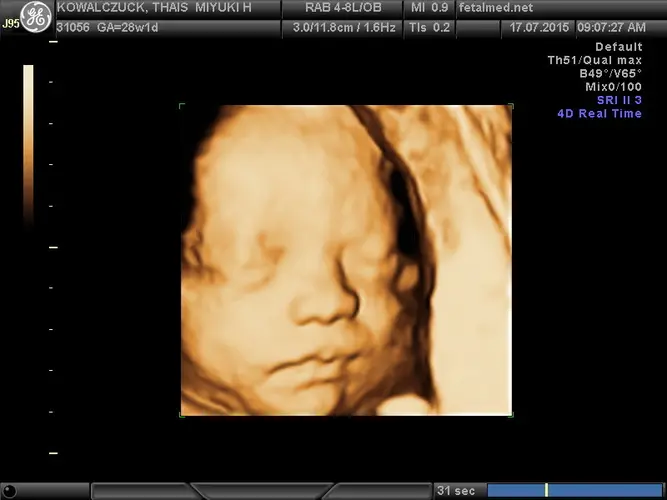

Uma das principais atividades do seu pequeno agora é treinar habilidades essenciais para a vida fora do útero. Ele pratica constantemente movimentos de respiração, deglutição e sucção. O reflexo de sugar está bem desenvolvido, e é comum vê-lo chupando o dedinho durante exames de ultrassom. Esses “exercícios” são fundamentais para garantir que ele esteja preparado para mamar e respirar após o parto.

A pele do bebê passou por uma transformação significativa – não é mais translúcida como nas semanas anteriores. Camadas de tecido gorduroso mais claro estão se depositando sob a pele, dando uma aparência mais rosada e opaca. Este processo é essencial para a regulação da temperatura corporal após o nascimento.